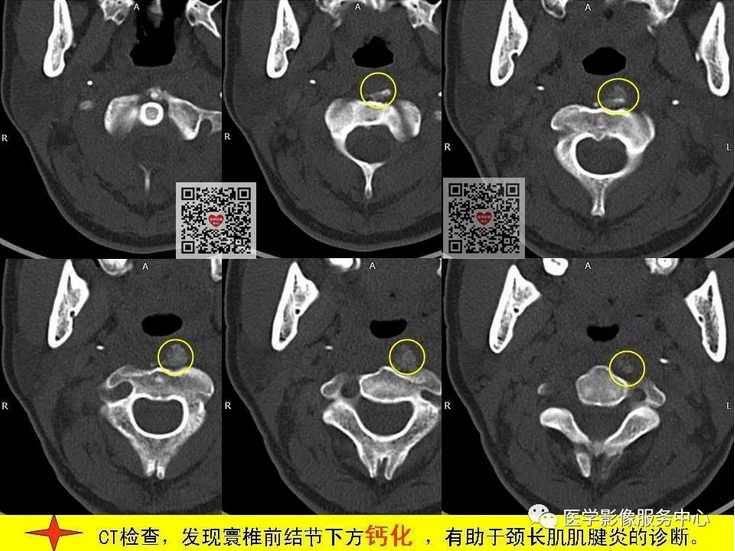

颈项疼痛是临床常见症状,最常见的原因就是颈椎病,包括颈椎骨质增生,颈椎间孔狭窄、颈间盘膨隆突出等表现,综合运用DR、CT、MRI这些影像检查方法,比较容易做出诊断,除此之外,引起颈项疼痛,还有比较少见的原因,不为影像诊断及临床医师所熟知,接下来我们看看下面的2个病例,比较少见的颈长肌肌腱炎。

颈长肌肌腱炎,是以颈项疼痛为主要临床表现的一种疾病,因颈长肌前方毗邻食道及咽部,常常伴发咽部疼痛和吞咽疼痛,临床及影像科医生对其认识较少,常易与其它引起颈项疼痛的疾病混淆 。

其病因为羟磷灰石结晶沉积于颈长肌上斜肌引起的炎性反应,以刺激组织渗出为主。羟磷灰石结晶沉积机制尚不十分明确,可能与损伤、组织坏死和炎症等因素相关。